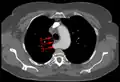

Aberrant subclavian artery at axial CT-scan. (1) trachea, (2) esophagus, (3) aberrant subclavian artery.